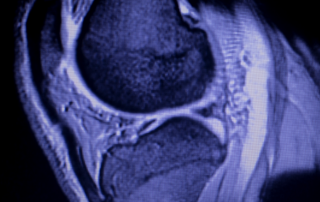

Menisküs Yırtığı Nedir? Menisküs yırtığı, dizde en sık meydana gelen, ağrılı ve zayıflatıcı bir kıkırdak